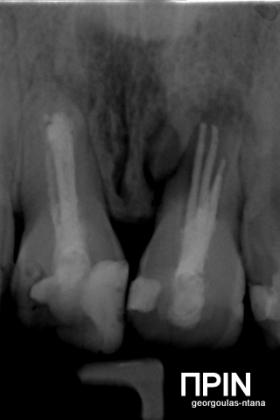

Στην ασθενή αυτή είχαν πραγματοποιηθεί 2 ενδοδοντικές θεραπείες (απονευρώσεις) που ακολουθήθηκαν από 2 ακρορριζεκτομές χωρίς επιτυχία. Η ασθενής ήταν δυσαρεστημένη με την όψη κ το χρώμα των δύο δοντιών και φυσικά με το πρόβλημα υγείας που δημιουργήθηκε. Πραγματοποιήθηκε εξαγωγή των δύο δοντιών, οστική αύξηση και τοποθέτηση 2 εμφυτευμάτων στις θέσεις των δύο κεντρικών τομέων. Τα δύο εμφυτεύματα αποκαταστάθηκαν με 2 υβριδικά κολοβώματα από διπυριτικό λίθιο και ολοκεραμικές στεφάνες ενώ στους 2 πλάγιους τομείς τοποθετήθηκαν επίσης ολοκεραμικές στεφάνες.